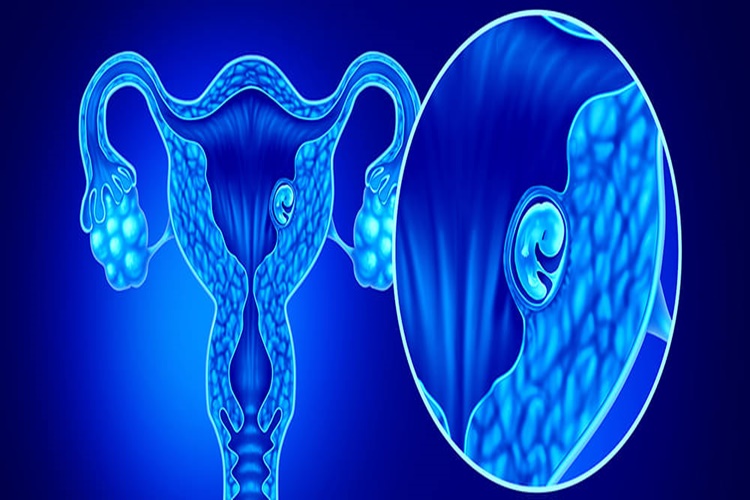

PCOS Genetik Midir?

Polikistik Over Sendromu (PCOS),hem genetik faktörlerin hem

de çevresel etkenlerin bir kombinasyonu sonucu ortaya çıkan bir durumdur.

Yapılan araştırmalar, PCOS'un genetik yatkınlığa sahip bireylerde daha sık

görüldüğünü göstermektedir. Ancak tam olarak PCOS'un nedeni tam olarak

bilinmemektedir ve genetik yatkınlığın yanı sıra hormonal ve çevresel

faktörlerin de etkili olduğu düşünülmektedir.

Ailesinde PCOS öyküsü olan kişilerde bu sendromu geliştirme

riski daha yüksek olabilir. Ancak genetik faktörler tek başlarına PCOS'u

açıklamamaktadır. Hormonal dengesizlikler, insülin direnci ve obezite gibi

faktörler de PCOS gelişiminde rol oynayabilir.

Sonuç olarak, PCOS'un gelişiminde genetik faktörlerin etkisi

olduğu düşünülmekle birlikte, bu yalnızca bir bileşenidir ve genetik yatkınlık,

diğer faktörlerle bir araya geldiğinde PCOS gelişim riskini artırabilir.

PCOS'un kesin nedenleri ve mekanizmaları hala tam olarak anlaşılamamıştır ve

araştırmalar devam etmektedir.